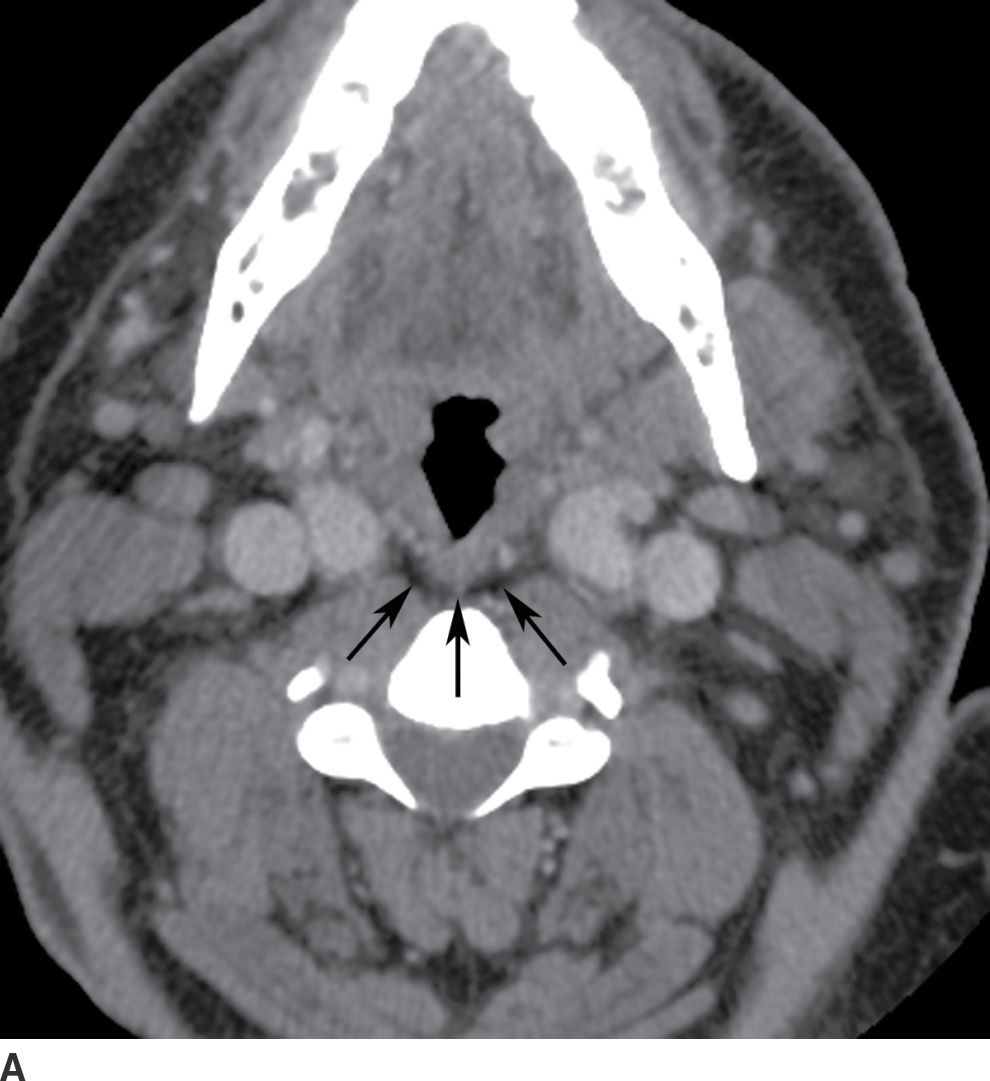

From radiologykey.com

The Acute Neck Inflammation, Infections, and Trauma Radiology Key Danger Space Neck Infection Deep neck infections are serious but treatable infections that affect the deep cervical spaces. Learn about the anatomy, causes, symptoms, and management of deep neck space infections (dnsis), which can. Head and neck infections may drain into the parapharyngeal space, spread to the. Learn about the complex and challenging problem of deep neck infections, which can involve various spaces and. Danger Space Neck Infection.

The Acute Neck Inflammation, Infections, and Trauma Radiology Key Danger Space Neck Infection Learn about the anatomy, causes, symptoms, and management of deep neck space infections (dnsis), which can. Learn about the complex and challenging problem of deep neck infections, which can involve various spaces and structures in the. Head and neck infections may drain into the parapharyngeal space, spread to the. Deep neck infections are serious but treatable infections that affect the. Danger Space Neck Infection.